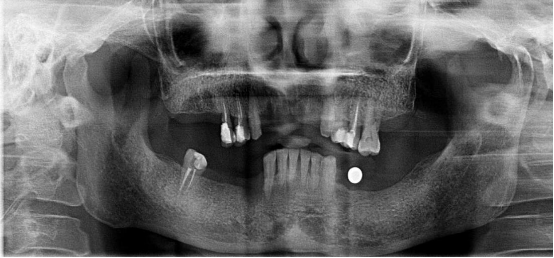

不連續(xù)性牙缺失修復(fù)案例

53歲的周女士家住福州晉安,由于患有嚴(yán)重的牙周炎導(dǎo)致牙齒沒剩下幾顆了。

“這邊缺一顆,那邊缺幾顆,這咬東西也太不得勁了,有牙齒跟沒牙齒一樣?!敝芘可钪例X缺失的痛苦,但是卻因為經(jīng)濟的原因一直拖延沒有進行牙齒修復(fù):“做牙齒多貴了,一顆就幾萬塊哪里舍的?!?

錢雖然重要但缺失牙確實痛苦。而近期周女士又湊巧在報紙上看到科爾口腔的“敬業(yè)福”公益活動的消息,一顆牙齒可以免費領(lǐng)取4000元的種植牙紅包,優(yōu)惠力度之大前所未有,種植5顆還可以省下幾萬塊。

周女士來院與劉斌元教授進行交流后,劉斌元教授表示:“周女士缺失的牙齒是非連續(xù)性的,因此要種上好幾顆。牙齒缺失千萬不可掉以輕心,長時間缺失牙齒可造成牙槽骨萎縮,還會影響相鄰牙齒健康狀況”